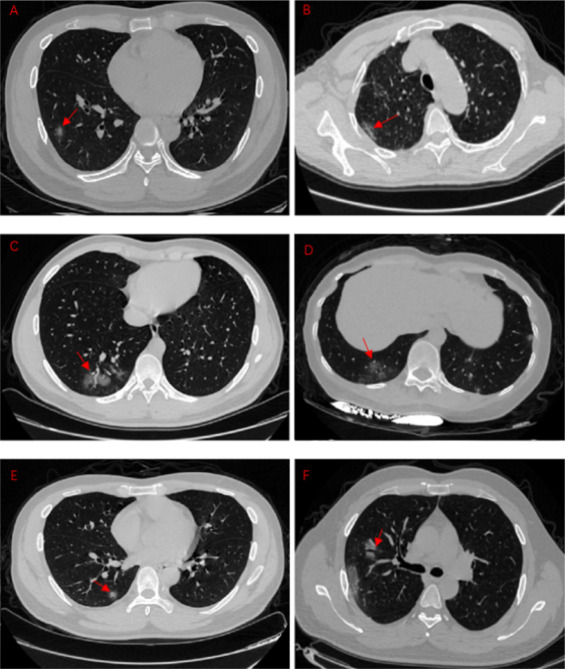

Y esto por qué? Image

Sabemos que la infección por SARS-CoV-2 induce daño pulmonar, incluso en casos #asintomáticos

⬇️

ncbi.nlm.nih.gov/pubmed/32294504